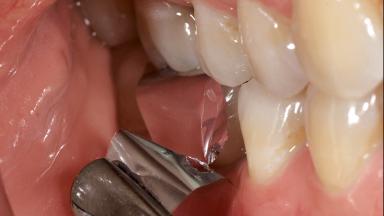

Occlusal Load—a Factor for Implant Failure?

In this case, Nicola Zitzmann describes the sudden loss of a previously well-osseointegrated implant that had been in healthy function for 5 years. The case includes recommendations for occlusion and function of implant restorations. A 74-year-old patient had received implant-fixed dental prostheses in the maxilla in 2008, and in the right mandible three years later. His tooth loss was mainly related to recurrent caries associated with hyposalivation as a potential side effect of his cholesterol-lowering medication.